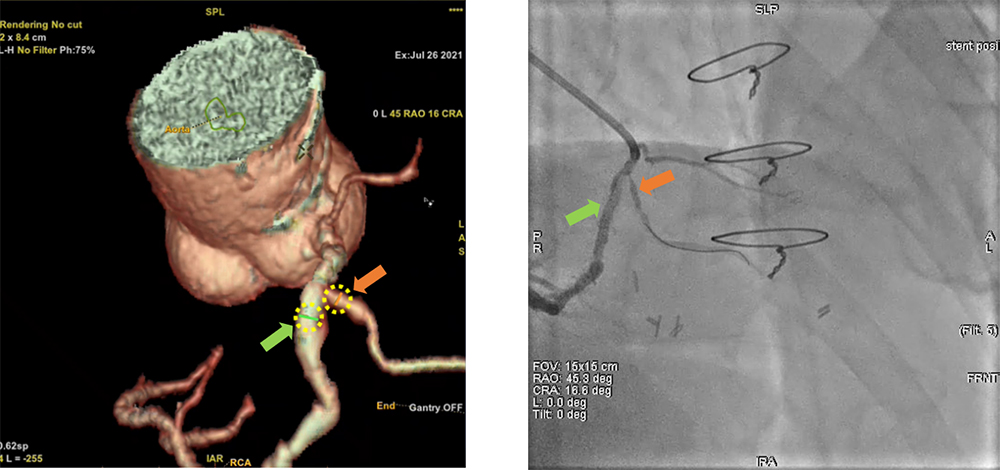

ワークステーションで作成したボリュームレンダリング(VR)画像とアームを同期連動する機能です。この機能にはVR画像を正面アームの角度に追従させて連動する機能とVR画像で決定した角度情報をアームに転送して連動させる機能があります。位置合わせを必要としないため簡便に利用できます。下図に使用例を提示します。術中に、「右冠動脈本幹と右室枝を分離できる角度を探してほしい」との依頼があり、VR画像上で右冠動脈本幹と右室枝の短軸にワイヤーフレームを表示させ、2つのワイヤーフレームが直線になる角度、すなわち分離の良い角度を確認した後、この角度をInnova Syncro 3D機能によって正面アームに連動させました。連動時のアーム挙動は、転送した角度に近い側のアームがポジション移動し、対側アームは直行する角度へポジション移動されます。

IGS620_kurume_07.jpg

VR画像で右冠動脈本幹と右室枝の短軸が分離できる角度を確認し、Cアームに角度情報を連動させた(RAO 45度、CRA 17度)